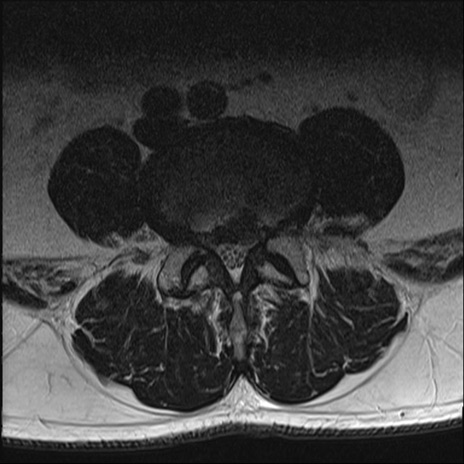

【整形】TIPS症例2 腰椎MRI T2WI(横断像)

【症例】70歳代男性

【主訴】左下肢痛

【現病歴】2週間前くらいから腰痛、左下肢痛あり。左臀部から大腿、下腿外側のしびれが常時ある。歩行とともに同部位の痛みあり。

【身体所見】Lasegue70-/60+、Bragard-/±、PTR ±/±、ATR -/-、IP 5/5、TA 5/4、TS 5/5、EHL 右第1足趾なし/3、FHL 5/5、hypersthesia(-)、足背動脈触知良好

異常所見と診断は?